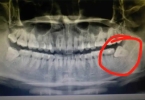

3、纯钛金属牙套的优势:纯钛金属牙套的价格在1000至1200元左右。虽然价格较高,但它们对影像学检查的影响最小,这意味着在做X光或其他牙科影像检查时,不会造成明显干扰。纯钛的生物相容性非常好,长期佩戴也不易引起口腔不适。